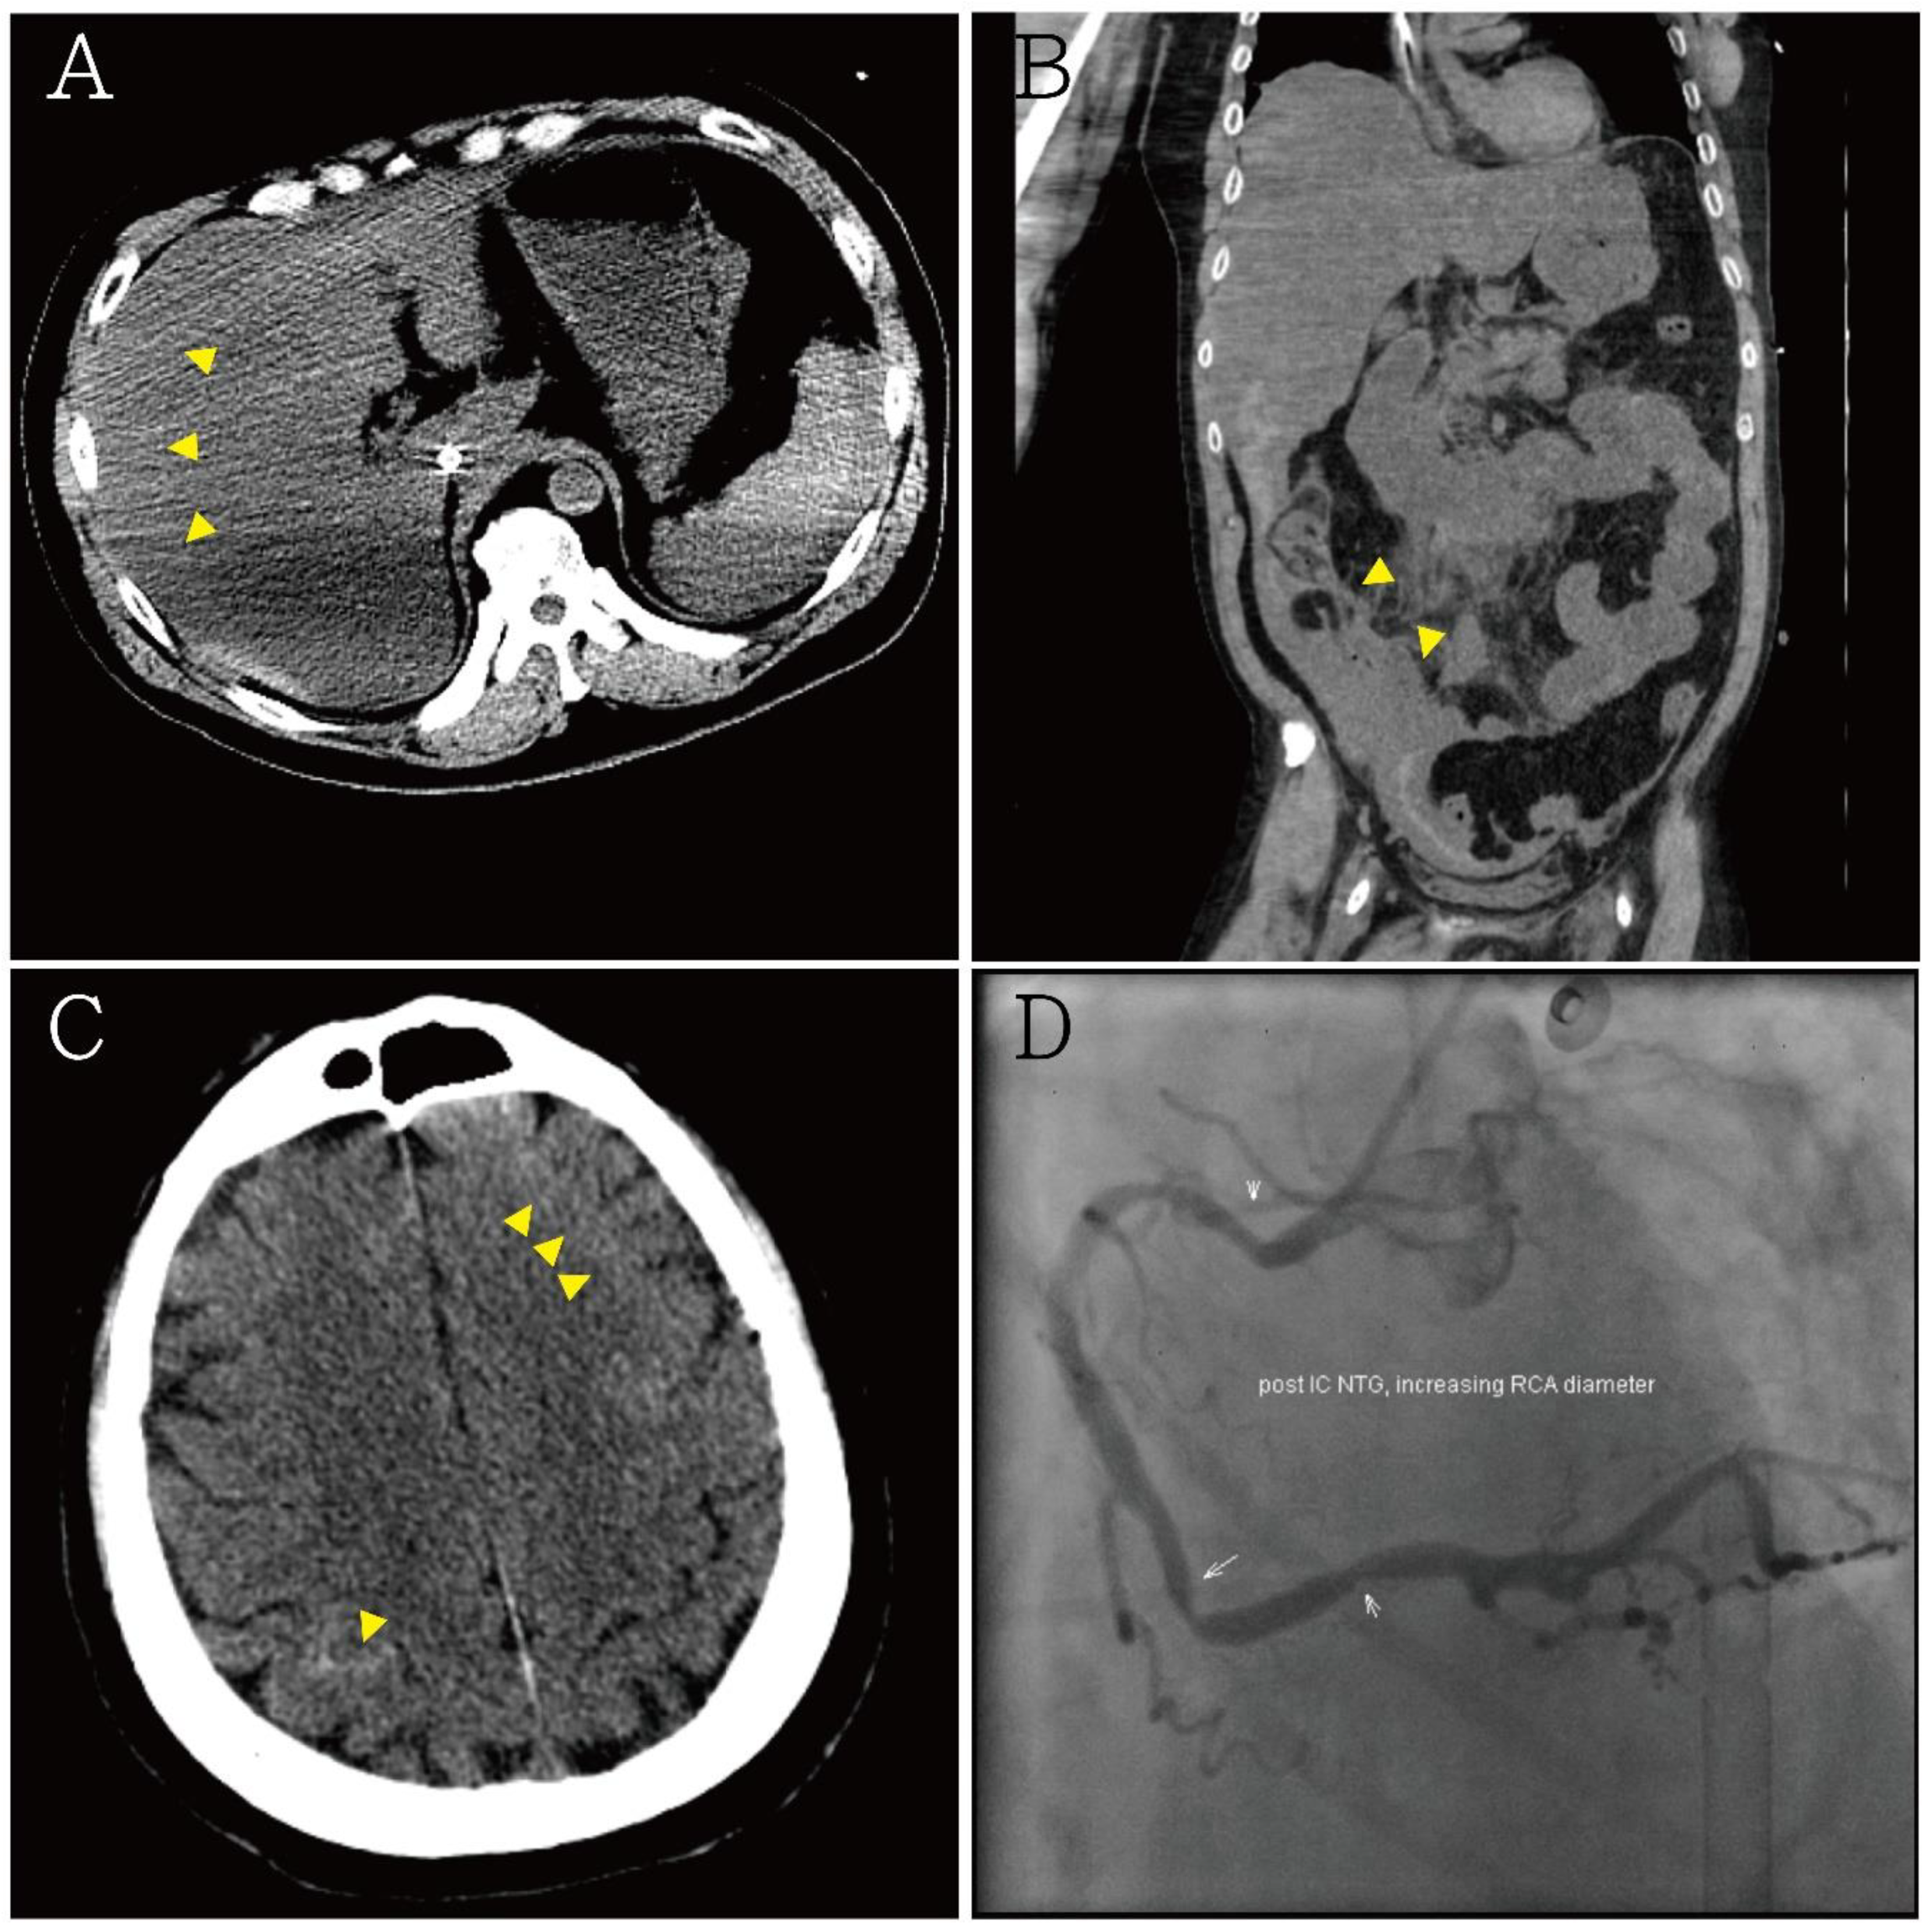

Figure 3.

(A,B) Abdominal computed tomography showing hemoperitoneum due to internal bleeding (yellow arrowheads), liver laceration was suspected; (C) brain computed tomography showing minimal bilateral sulci subarachnoid hemorrhage (yellow arrowheads); (D) diagnostic coronary angiography showing only coronary artery spasm and native left and right coronary artery diameters with an increased myocardial bridge after intra-coronary nitroglycerin injection. There was no occluded segment or flow-limiting lesion.

A 54-year-old man presented with loss of consciousness and persistent bradycardia after a traffic accident. He had a history of hypertension and was on regular medications. He had no history of cardiovascular disease at a personal and family level. He was observed to have facial abrasions and epistaxis. He had no cerebrospinal fluid otorrhea or rhinorrhea, and no deformity of the extremities. After being admitted to the emergency department, he was noted to have bradycardia (40–46/min), and his blood pressure could not be detected. After four minutes, the cardiac monitor showed pulseless electrical activity. Timely cardiopulmonary resuscitation was performed, and the patient returned to spontaneous circulation. On neurological examination, his Glasgow Coma Scale score was E1VTM1, and he had a 3.5 mm bilateral pupil size without light reflex. An electrocardiogram (ECG) revealed ST-segment elevation in leads II and V3-6, with a spiked helmet sign (Figure 1). Acute myocardial infarction was suspected. Bedside cardiac ultrasound revealed grossly normal wall motion of the left ventricle under inotropic agents. The interventricular septum and left ventricular posterior wall thickness were noted, and there was no pericardial effusion. A follow-up ECG revealed atrial fibrillation with a rapid ventricular response and ST-segment depression in V2-6 (Figure 2). Cardiac enzyme studies revealed no elevation of the level of the highly sensitive troponin I (5.5 pg/mL (normal range <17.5 pg/mL). Abdominal computed tomography revealed hemoperitoneum due to internal bleeding (Figure 3A,B). Liver laceration was suspected. Brain computed tomography revealed mild cortical brain atrophy and minimal bilateral sulci subarachnoid hemorrhage (Figure 3C). The patient was promptly placed on extracorporeal membrane oxygenation (ECMO) due to a poor response to inotropic agents. Diagnostic coronary angiography revealed only coronary artery spasm and a myocardial bridge of the left anterior descending artery (Figure 3D). There were no occluded segments or flow-limiting lesions. After the administration of an intracoronary nitroglycerin injection, the native left coronary artery and right coronary artery diameters significantly increased. A left ventriculogram showed mild mitral valve regurgitation and mild hypokinesia of the inferior wall. The left ventricular ejection fraction was 60% under ECMO and inotropic agents. However, even with adequate resuscitation, the patient remained with a low cardiac output and progressively went into shock; he eventually died.